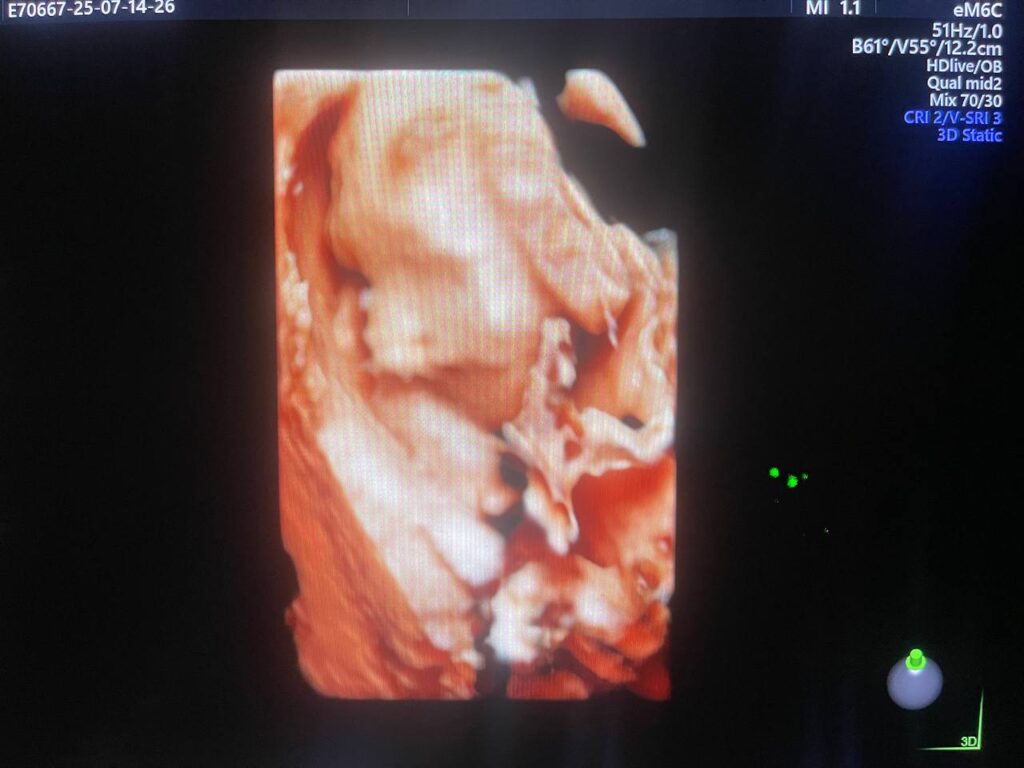

Multiple Craniofacial anomaly seen , mild dilated posterior atrium of the lateral ventricle 10.3mm , agenesis of the corpus callosum ??can not be excldued , bilateral cleft lip & palate , small orbits & hand anomaly , congenital heart disease can not be excldued , please for further study & echocardiography , Patau Syndrome? (Trisomy 13 ? ) can not be excldued ? please further study , no other anomaly can be detected now